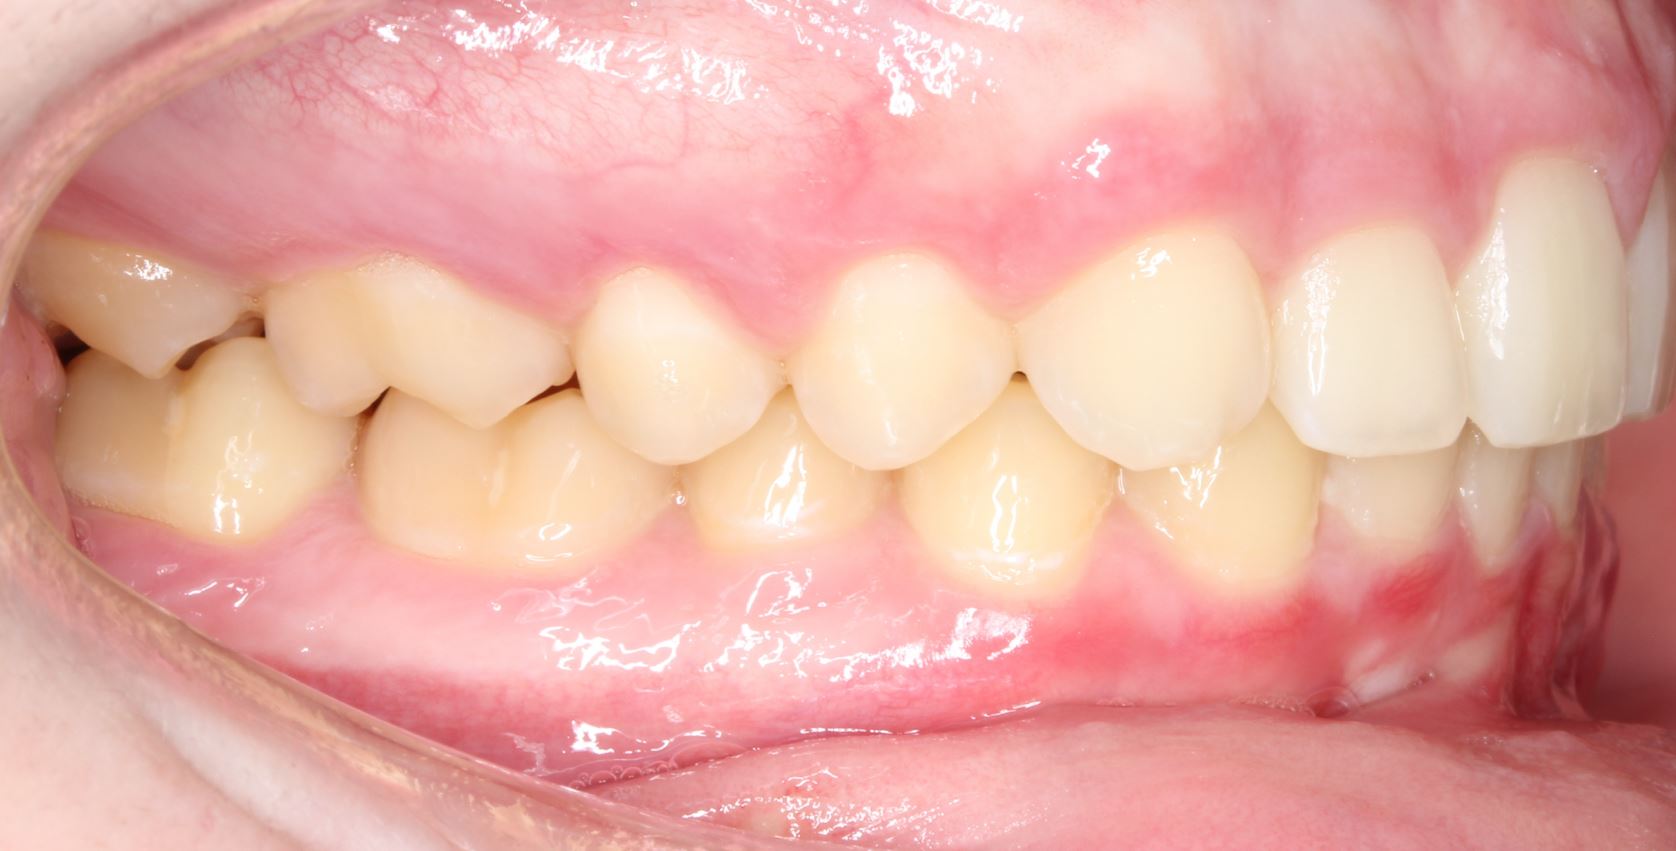

Same Patient as Above